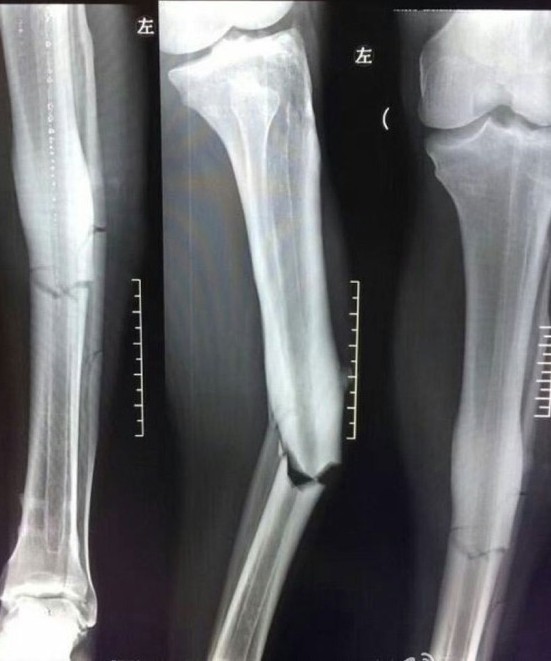

Çin'de dün oynanan Şangay Shenhua-Şangay Sipg karşılaşmasında Beşiktaş'ın eski yıldızı Demba Ba'nın ayağı kırıldı.

İlk tetkikleri yapılan Demba Ba için açıklama geldi. Shougang Hastanesi'nden ortopedi uzmanı Zhang Guang-wu, Demba Ba'nın futbola yeniden dönmesinin zor olduğunu ve araba kazasıyla eşdeğerde bir sakatlık yaşadığını kaydetti.

Zhang Guangwu, "Demba Ba'nın iyileşmesi 1 - 1.5 yıl sürebilir. Belki sahalara dönmesi 2.5 yılı da bulabilir. İlk ameliyat sonrasında 4 ay zaman geçecek ve ikinci bir ameliyat daha olacak ve bu da en az 1 yıl zaman alır. Otomobil kazasıyle eşdeğer bir durumla karşılaştı" dedi.

Demba Ba'nın sahalara dönmesine pek umut vermeyen uzman, "31 yaşındak oyuncunun yaşadığı bu sakatlık, bir düşüşe de yol açacaktır" sözleriyle bir nevi futbolcunun güçlü olması gerektiğini ancak eski günlerine dönmesinin mümkün olmadığını belirtti.